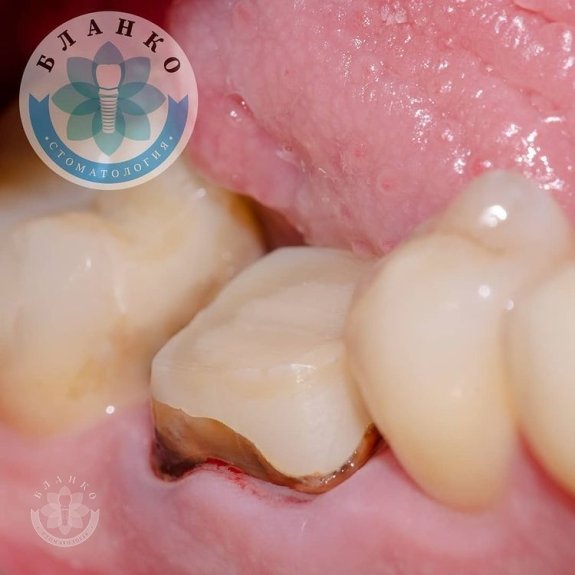

✳️На начальном снимке мы видим зуб 4.6 ( обведен красным цветом ),в котором наблюдается хроническое воспаление вокруг корней зуба и плохая реставрация из пломбировочного материала, которая давно отошла от тканей зуба и под которой развился вторичный кариес ( снимок №2 ).

— убрана несостоятельная реставрация

— извлечены анкерные штифты